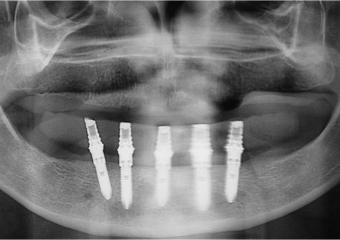

Raio X dos implantes inferiores - Clínica Cliniface

Raio X dos implantes inferiores